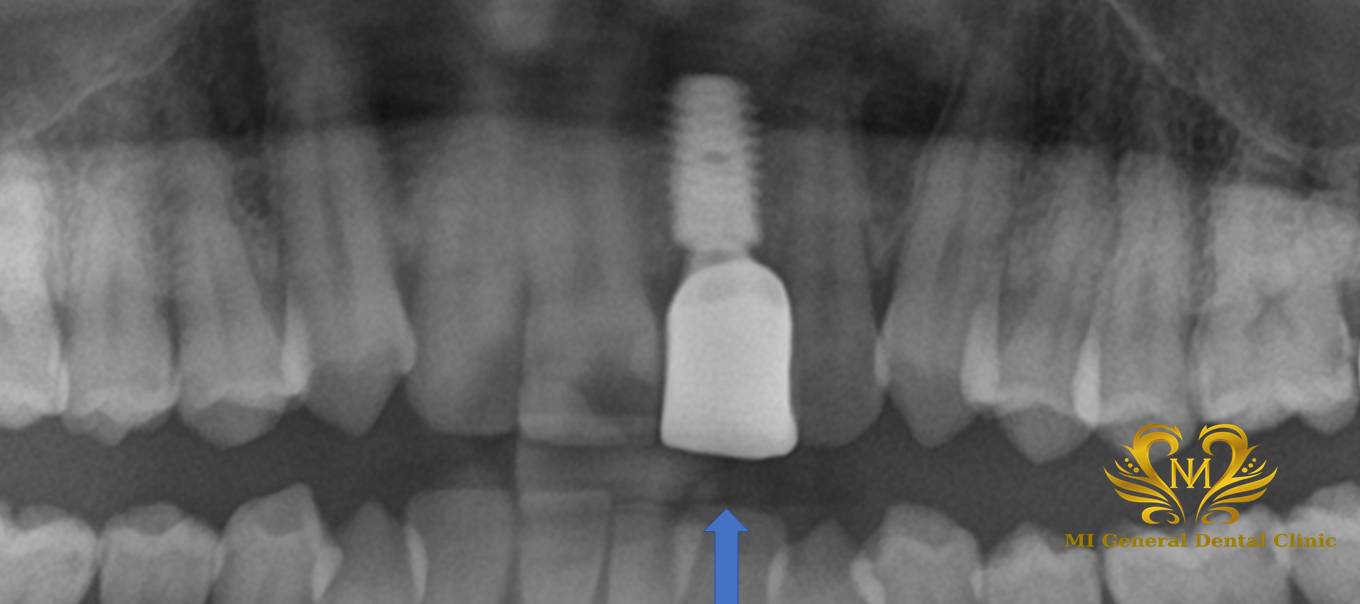

治療後

今回の手術後は、インプラントが顎の骨としっかり結合するまで約4か月間待ちます。

4か月後に、インプラントが骨にしっかり固定されていることを確認したうえで、再度仮歯を作製。

仮歯の状態で生活していただくことにより形の要望についてイメージをしていただき、その後、実際の被せ物のかたどりをします。

完成した被せ物を装着し、しっかり噛める状態に回復しました。

今回のケースでは、初診から約10か月で最終的な被せ物まで治療が完了しました。